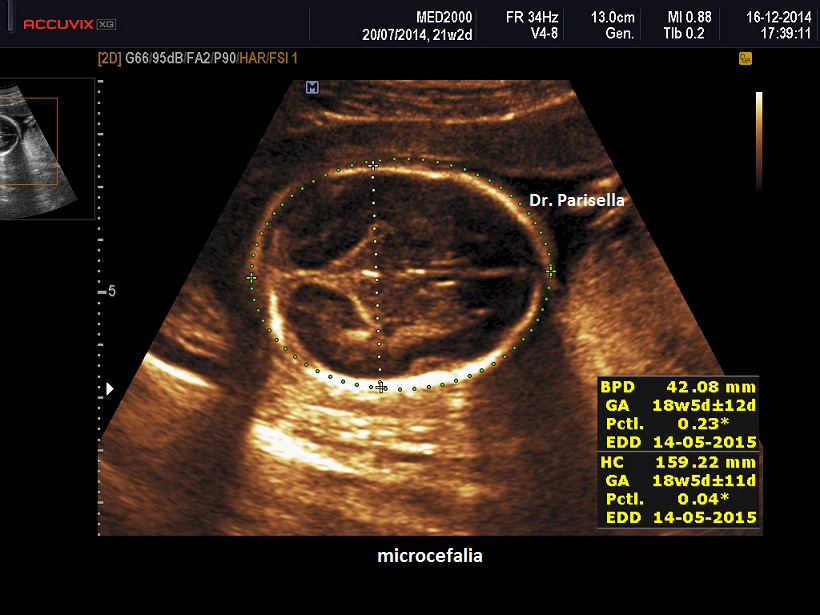

Agenesia del corpo calloso - microcefalia - bassa statura o Sindrome di Da Silva

E' caratterizzata da ipoplasia del corpo calloso, microcefalia, grave deficit cognitivo, appendici cutanee preauricolari, camptodattilia, ritardo di crescita.